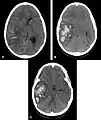

- Hémorragie cérébrale : la principale manifestation clinique de l'angiopathie amyloïde est l'hémorragie intracérébrale de topographie lobaire ou cérébelleuse[7]. La topographie lobaire regroupe les structures corticales et sous-corticale (c'est-à-dire proche de la surface du cerveau). Elle est principalement définie par opposition à la topographie profonde qui englobe essentiellement les ganglions de la base (en particulier le thalamus ou le noyau lenticulaire) et le pont. Cette distinction topographique est importante dans la mesure où l'hémorragie cérébrale lobaire est très évocatrice d'AAC alors que l'hémorragie cérébrale profonde est plutôt évocatrice de microangiopathie hypertensive. Cette distribution reflète l'atteinte préférentielle des petits vaisseaux corticaux dans l'AAC et de artères lenticulo-striées dans l'angiopathie hypertensive[8]. Cependant, parmi l'ensemble des topographies lobaires possibles, l'atteinte du lobe temporal ou occipital semble prédominante, en particulier si le patient avait déjà présenté une hémorragie dans ces régions[9]. Comme pour l'ensemble des AVC, les symptômes associés aux hémorragies cérébrales de l'AAC sont variables. Ils dépendent avant tout de la taille de l'hémorragie et de sa localisation.

Scanner cérébral objectivant une hémorragie profonde (thalamique gauche) plutôt évocatrice d'une angiopathie hypertensive